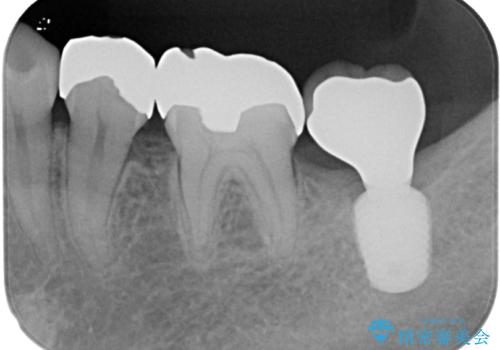

長い期間歯が欠損していた下顎奥歯に、インプラント埋入と同時に仮歯を装着すると(埋入即時荷重インプラントを行うと)、舌の付け根で仮歯を横向きに押してしまい、インプラントが脱落する危険性が高くなります。

インプラント埋入時に、装着できる状態の仮歯を用意するものの、埋入後すぐには加重させず、インプラントが無事に生着したことを確認した後に装着することで、危険を回避しつつ外科処置や痛みの少ないスムーズな治療を行うことができます。